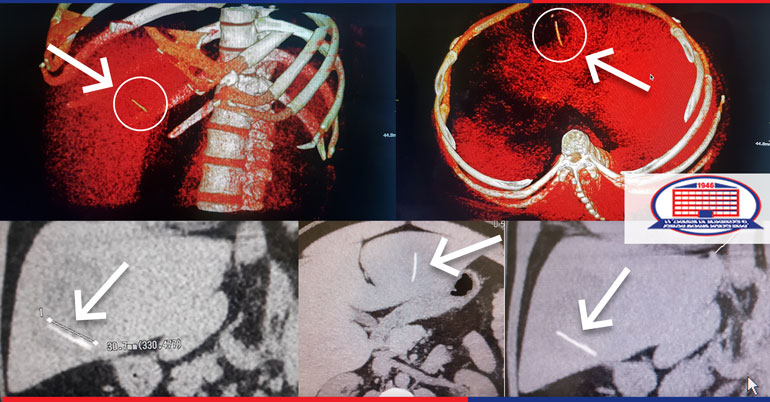

უჩიოდა მარჯვენა ფერდქვეშა არეში ყრუ ტკივილს, ჰქონდა მაღალი ცხელება. გასინჯვით პაციენტს მწვავე მუცლის სიმპტომები არ აღენიშნებოდა, მაგრამ ქირურგთა ჯგუფმა მიზანშეწონილად მიიჩნია მუცლის ღრუს კომპიუტერული ტომოგრაფია. კვლევა ჩატარდა კლინიკის კომპიუტერული ტომოგრაფით Toshiba aquilion RXL–ით, რომელიც თავის კლასში უპირობო ლიდერია. გამოვლინდა ღვიძლის აბსცესი. აღსანიშნავია ისიც, რომ ქირურგიის ეროვნული ცენტრის რადიოლოგმა ვასილ გერგედავამ აბსცესის ღრუში უცხო წარმონაქმნი შენიშნა.

ჩატარდა გადაუდებელი ოპერაცია – ლაპარატომია, აბსცესის ღრუს დრენირება, ინახა კუჭ–ღვიძლის ფისტულის არსებობა, ხოლო აბსცესის ღრუდან ქირურგებმა ამოიღეს საკმაოდ დიდი ზომის თევზის ფხა. ოპერაცია შეასრულეს ჩვენი კლინიკის ქირურგებმა გიგო ფიჩხაიამ და შოთა ძაგანიამ.